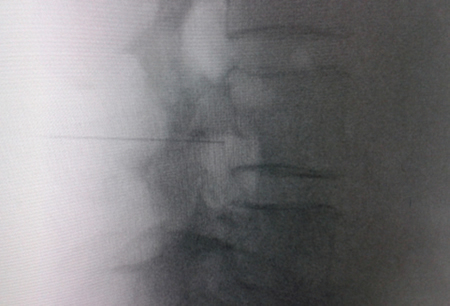

El acceso por vía transforaminal es el más utilizado (4). Se coloca al paciente en decúbito prono con una almohada a nivel abdominal para revertir la lordosis fisiológica. Las agujas o cánulas de radiofrecuencia que utilizamos con más frecuencia son de diámetro 20 o 22 G de 98 mm de largo con punta activa de 0,5 o 1 cm. Después de la asepsia con clorhexidina alcohólica y la colocación de campos estériles, se realizan enfoques radiológicos en incidencia anteroposterior, oblicuo y lateral. En incidencia anteroposterior y moviendo el arco en dirección cráneo caudal se borra el doble arco del borde inferior vertebral. En incidencia oblicua entre 20 y 30 grados ipsilateral al GRD a tratar, se visualizará la clásica imagen descrita como de “Scotty Dog”, que es resultado de acercar el macizo facetario y la apófisis espinosa al lado contralateral. El punto de entrada será entonces inmediatamente debajo del pedículo. Previa anestesia local con lidocaína al 1 %, la aguja se introducirá siguiendo una visión túnel y no se avanzará más allá de la mitad del pedículo en esta proyección con la finalidad de prevenir la lesión neural. En proyección lateral, se introducirá en el techo del neuroforamen

Fig. 1. Vista radiológica de perfil que muestra una cánula de radiofrecuencia en el ángulo anterosuperior o techo del neuroforamen, topografía aproximada del ganglio de la raíz dorsal